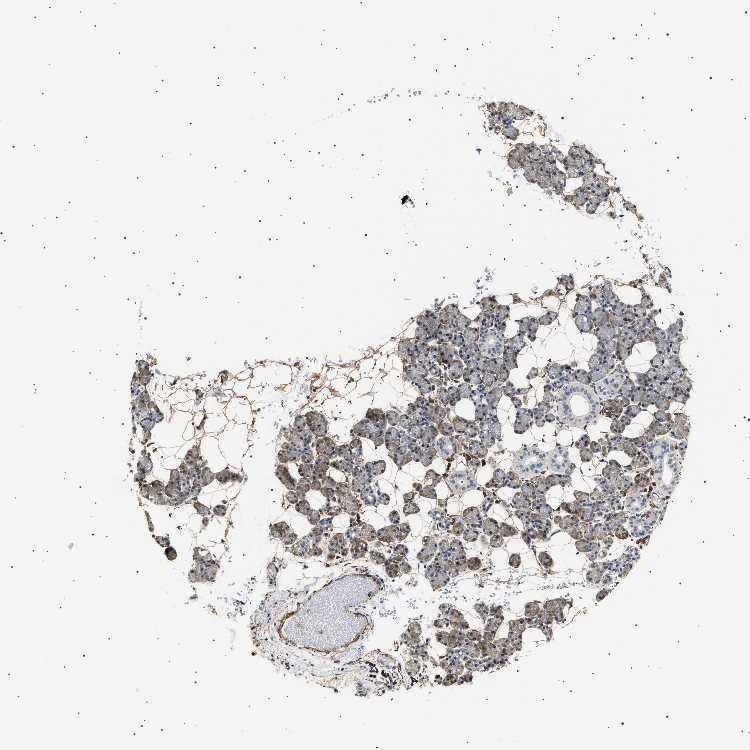

SALIVARY GLAND - Antibody stainingi

Antibody staining in the annotated cell types in the current human tissue is reported as not detected, low, medium, or high, based on conventional immunohistochemistry profiling in selected tissues. This score is based on the combination of the staining intensity and fraction of stained cells.

Each image is clickable and will lead to virtual microscopy that enables deeper exploration of all samples and also displays staining intensity scores, fraction scores and subcellular localization as well as patient and tissue information for each sample.

Antibody HPA020386

Glandular cells Low